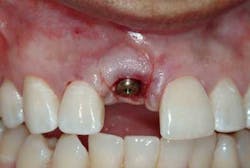

Now comes the tricky part — the provisional. Prosthetic control of peri-implant tissue is achieved by properly utilizing your abutment and provisional form. When placing the provisional, it is important to maintain gingival zenith. When fabricating a provisional, my rule of thumb is to create a flat or slightly convex surface facially and lingually, and a concave surface interproximally. This will minimize impingement on the tissue interproximally and, if anything, allow for “overgrown tissue” to develop. This tissue can be easily contoured prior to final placement to give an ideal esthetic gingival architecture.